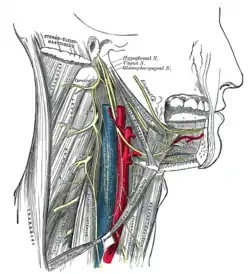

Muscles of the neck. Lateral view. Hypoglossal nerve, cervical plexus, and their branches.

Hypoglossal nerve, cervical plexus, and their branches. The right brachial plexus with its short branches, viewed from in front.